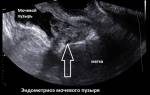

• При поражении эндометриозом мочевого пузыря или прямой кишки болезненное мочеиспускание и дефекация;